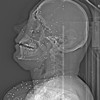

Bu görüntüler, güvenlik güçlerinin yüksek kalibreli silahlar ve saçma kullandığı yönündeki iddiaları destekliyor. Röntgenlerin büyük bir kısmında protestoculara karşı "birdshot" olarak bilinen bir mühimmatın kullanıldığı ifade ediliyor.

Balistik uzmanları bazı görüntülerde vücuttaki mermilerin AK-47 ve KL-133 gibi taarruz tüfeklerinde kullanılan mermilere benzediğini belirtti.

Saldırıların daha çok yüz, göğüz ve genital bölgede yoğunlaşması da dikkat çekti. 2022'de patlak veren "Kadın, Yaşam, Özgürlük" protestolarında da benzer bir örüntü oluşmuştu.

Guardian'a konuşan İranlı doktorlar, protestocuların özellikle göz, göğüs ve genital bölgelerinin hedef alındığını belirtmişti. Bazı sağlık çalışanları, çok sayıda hastada görme kaybı yaşandığını, aralarında çocukların da bulunduğunu aktarmıştı.